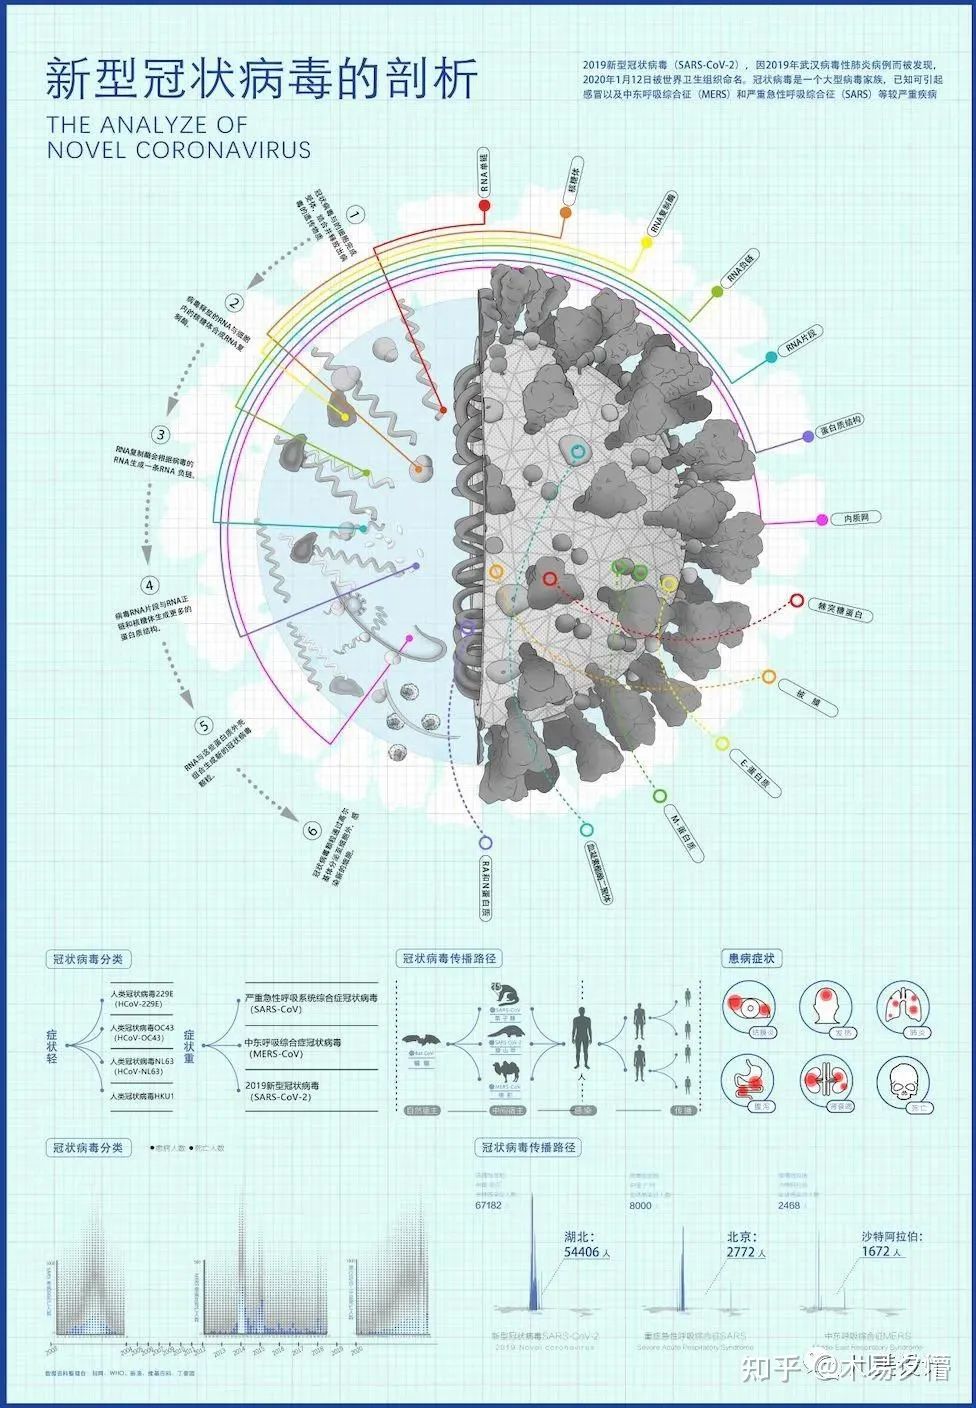

《新型冠状病毒的剖析》

作者:林霞秋,王杰 | 四川美术学院 | 数字媒体艺术

设计说明:本作品运用信息和数据可视化方式,详细分析解读2019年新型冠状病毒肺炎的生成过程、传播途径、感染症状、病毒比对。第一部分为主体,用生物图例搭配文字说明形式,阐释感染过程、剖析病毒结构。第二部分分成三个小部分,分别介绍目前能够感染人类的七类冠状病毒,并按轻重症状进行划分;病毒的传播过程和媒介;感染冠状病毒后的临床症状。第三部分是数据对比,将历史上造成严重传染和伤亡的三种冠状病毒进行多维度的对比,清晰显示三者间的异同。